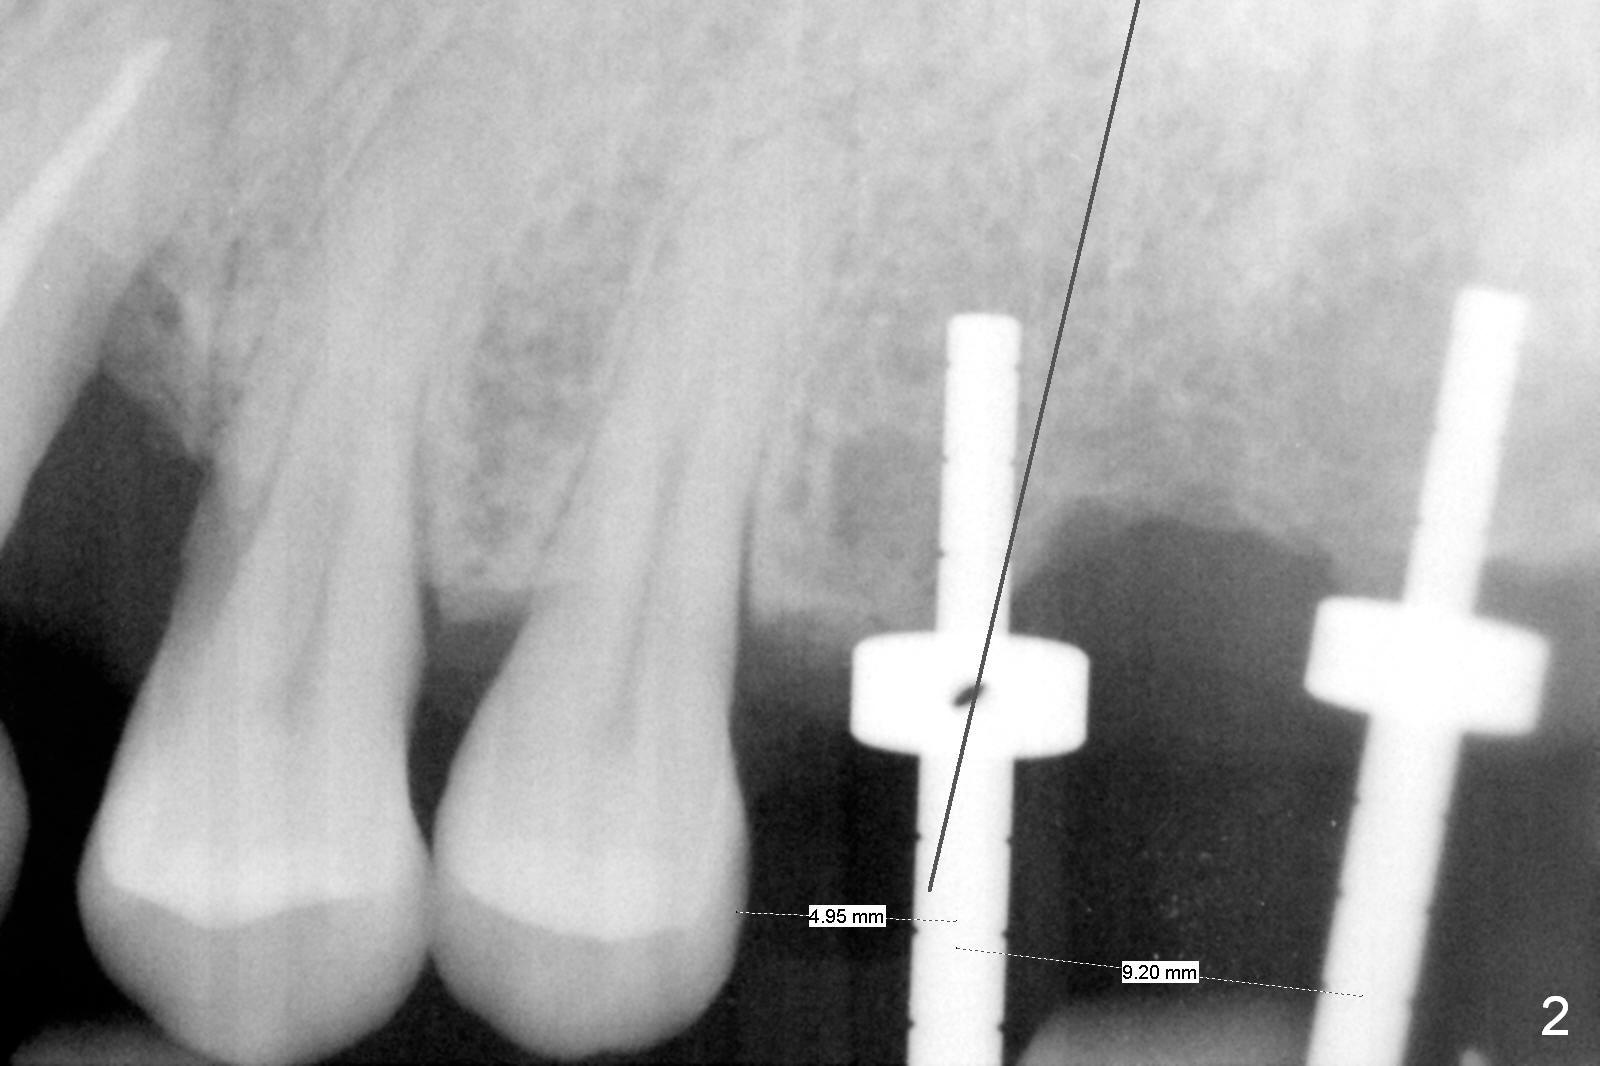

As shown by CT, the ridge at #14 is narrower than that of #15 (confirmed after incision), whereas the density at #14 is higher than that of #15. The osteotomies are established by combination of magic osteotomes and drills after change in trajectory (Fig.1-3). Following placement of 4.5x13 and 5x13 mm IBS implants and 6x4(3) and 6.5x4(3) mm pair abutments at #14 and 15 (Fig.4), flaps are sutured for hemostasis. Since the patient does not tolerate the surgery too well (unstable hypertension and oozing), immediate provisional is delayed. Periodontal dressing is applied instead. While the implants are healing, porcelain chips at the upper anterior bridge. There appears no bone resorption 6 months postop (Fig.5). Impression is taken following changing abutment to 5x4(2) mm at #14 and Diode gingivectomy. A panoramic film is taken 1 year 2 months post cementation. CT taken 2 years post cementation shows relatively good trajectory of these 2 implants (Fig.6,7).